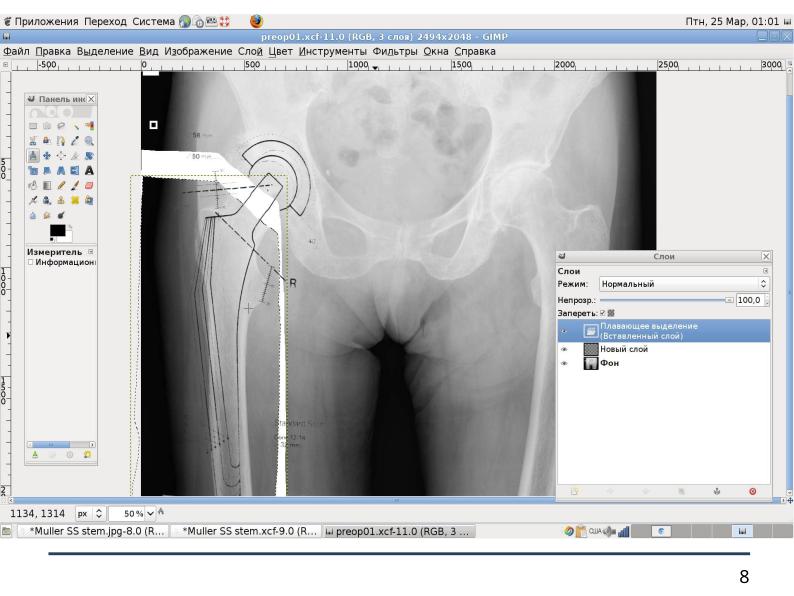

Файл:Использование СПО в планировании ортопедических оперативных вмешательств (Анатолий Якушин, OSSDEVCONF-2025).pdf

Использование_СПО_в_планировании_ортопедических_оперативных_вмешательств_(Анатолий_Якушин,_OSSDEVCONF-2025).pdf (793 × 595 пикселей, размер файла: 1,14 МБ, MIME-тип: application/pdf, 18 страниц)